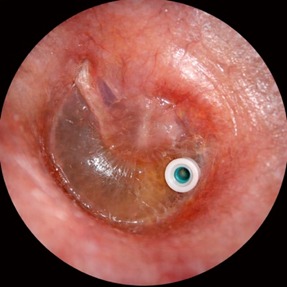

Surgical

Grommets (ventilation tubes), adenoidectomy.

If fluid persists beyond 3 months or significant hearing loss is present: Myringotomy with grommet insertion and/or adenoidectomy (if enlarged adenoids). These are short, safe procedures that significantly improve hearing and quality of life.

Grommets are tiny ventilation tubes placed in the eardrum during a short procedure under general anesthesia. They allow fluid to drain and equalize pressure.